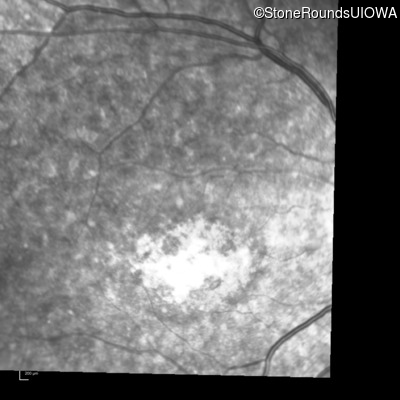

Infrared Fundus Photograph - Right - 10/160

Exemplar